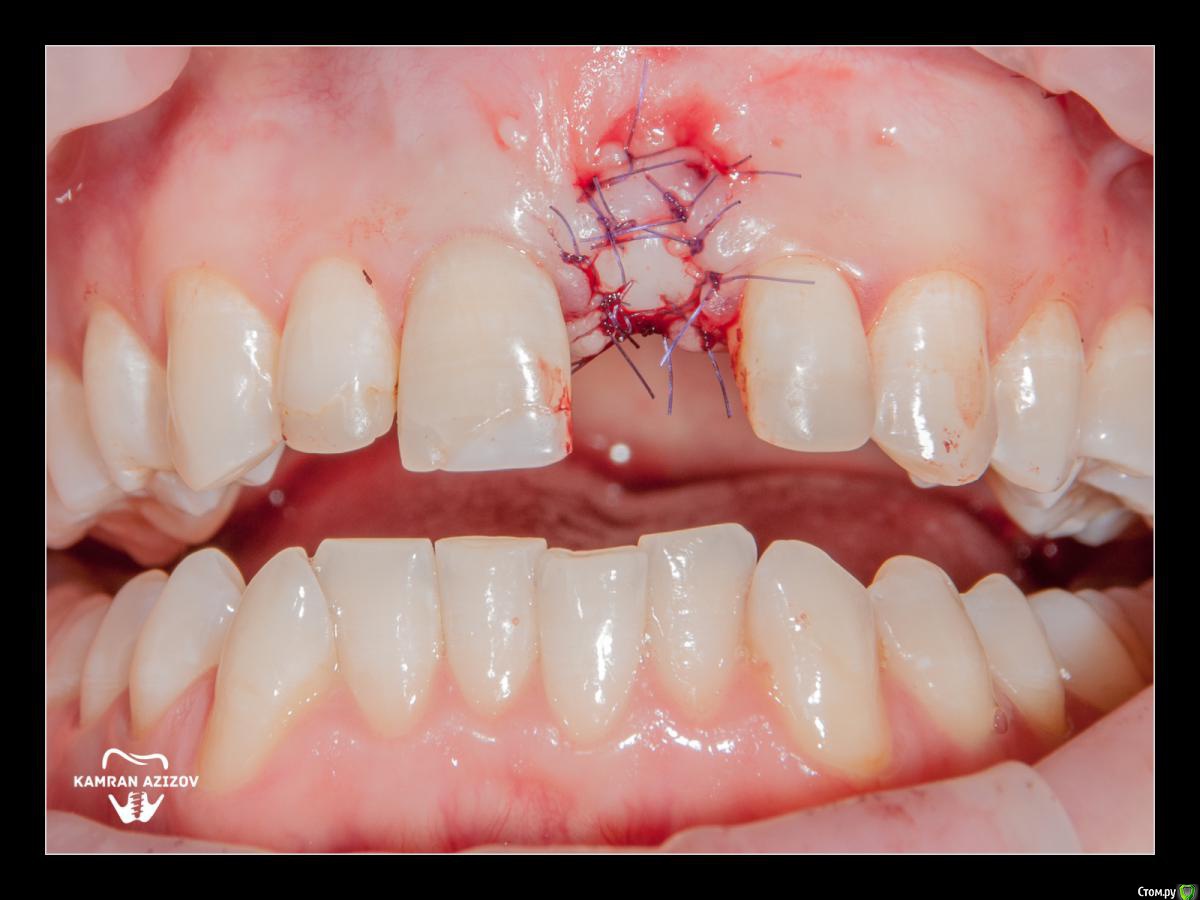

kamranchick Опубликовано 8 октября, 2019 Поделиться Опубликовано 8 октября, 2019 удаление зуба+консервация лунки с вестибулярным ССТчерез 2 месяца имплантация с фдм по карлоссучерез 4 месяца замена на более длинный фдм и широкийпостоянная коронка 5 Ссылка на комментарий

Irouil Опубликовано 9 октября, 2019 Поделиться Опубликовано 9 октября, 2019 Жаль фотки до удаления нет, кажется там дефект вестибулярно был Ссылка на комментарий